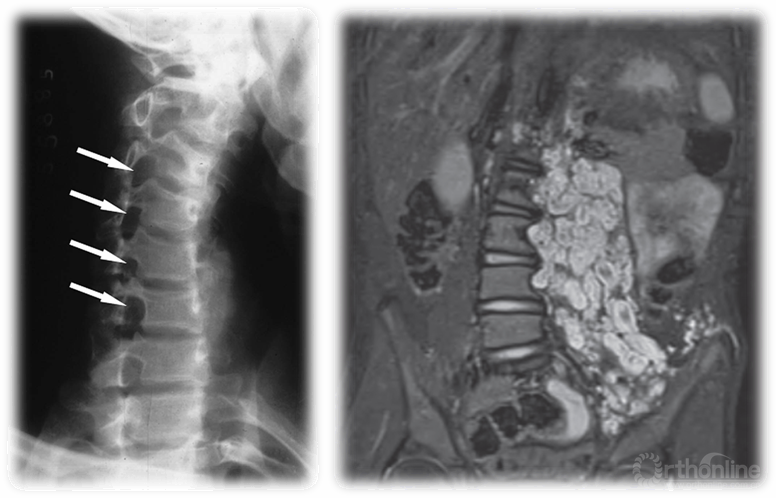

Syndromic:

● Certain syndromes, such as Marfans, Ehlers-Danlos and other connective tissue disorders, as well as neurofibromatosis, Prader-Willi, and many bone dysplasias may be associated with EOS.

综合征型:

● 某些综合征,比如马凡氏综合征,埃-当综合征和其他结缔组织疾病,还有神经纤维瘤病,Prader-Willi综合征,以及许多骨发育不良都可能与EOS有关。

神经纤维瘤病

Evaluation of EOS:

● Plain X-rays are sufficient to make the diagnosis of EOS.

● MRI may be indicated for curves that are larger than 20 degrees or progressive, or if there are signs or symptoms of neurologic problems and in persistent or progressive infantile idiopathic scoliosis. Intraspinal abnormalities are commonly associated with EOS, particularly congenital scoliosis.

● CT best helps visualize bone anatomy in congenital scoliosis, and is often useful for surgical planning, but must be weighed against risk of radiation to young child.

EOS的评估:

● 普通的X线检查足以诊断EOS。

● MRI可提示超过20度的侧凸或侧凸的进展,或者有迹象或症状的神经问题,以及处在稳定或进展的幼儿特发性脊柱侧凸。脊柱的异常通常与EOS有关,特别是先天性脊柱侧凸。

● CT是最有助于使先天性脊柱侧凸的骨骼解剖得到可视化,通常也对手术方案的制定有所帮助,但必须权衡给年轻孩子带来的辐射风险。